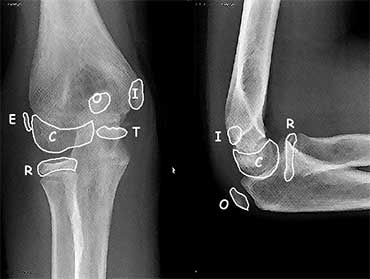

Elbow X-ray (peds)

Elbow Ossification by Age (CRITOE)

| Ossification Center | Age of Appearance (add 1yr for boys) |

| Capitellum | 1yr |

| Radial head | 3yr |

| Internal epicondyle | 5yr |

| Trochlea | 7yr |

| Olecranon | 9yr |

| External epicondyle | 11yr |

Reading Film

- Anterior humeral line should intersect with middle third of capitellum

- If not, consider supracondylar fracture or lateral condyle fracture

- Line drawn along axis of radial head and neck should pass through middle of capitellum

- If not, consider fracture of lateral condyle, radial neck, Monteggia, or elbow dislocation

- Fat pads

- Anterior may be normal or if large may be abnormal ("sail sign")

- Posterior is always abnormal